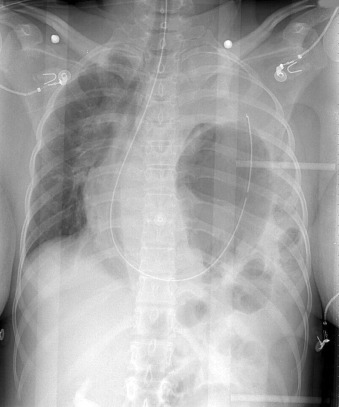

Of all traumatic lesions to the thoracic cardiovascular system, the most predictable one is blunt deceleration/acceleration traumatic injury to the thoracic aorta, resulting in a false aneurysm-type lesion, typically of the isthmus proximal descending aorta. It may also involve the ascending aorta, the supradiaphragmatic aorta, or the innominate artery take-off ( Figs. 28-1 to 28-13 ).